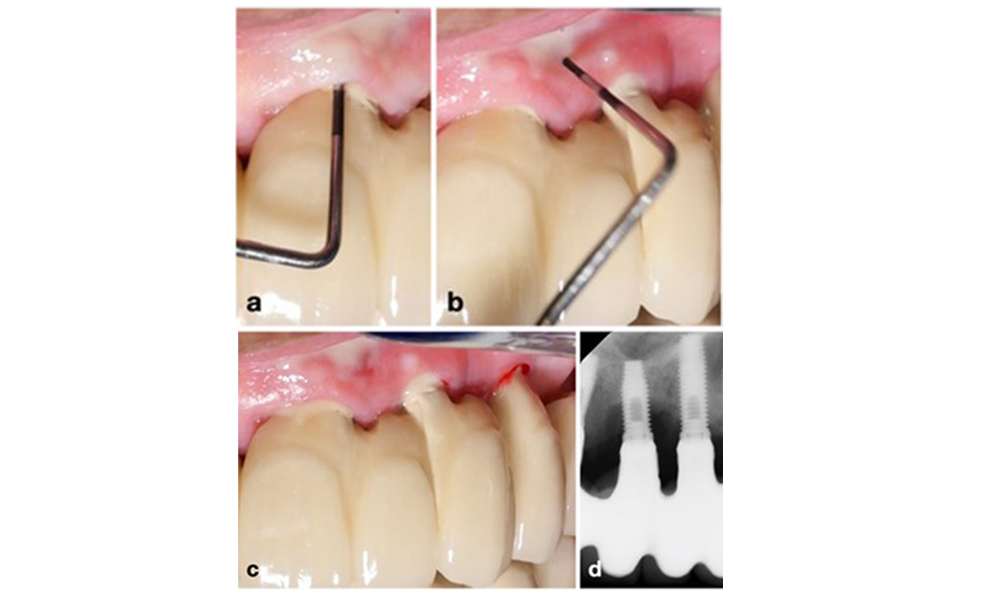

Auf dem World Workshop on the Classification of Periodontal and Peri‐Implant Diseases and Conditions 2017 wurden diagnostische Kriterien für periimplantäre Mukositis und Periimplantitis festgelegt (Renvert et al. 2018). Periimplantäre Mukositis ist definiert als (1) Entzündung um das Implantat (also Rötungen, Schwellungen, Blutfäden oder Blutstropfen innerhalb von 30 Sekunden nach dem Sondieren), jedoch (2) ohne zusätzlichen Knochenverlust nach der Ersteinheilung (Abb. 1).

Implantat an Position 26 mit periimplantärer Mukositis (a-c). Die Sondierungstiefe von 5 mm (b) stimmt mit der wenige Wochen nach dem Einsetzen der prothetischen Rekonstruktion vorgenommenen Messung überein. Es kommt zwar zu einer Sondierungsblutung (c), aber die Röntgenaufnahme zeigt keinen weiteren Knochenverlust über das Maß hinaus, das bei einer marginalen Knochen-Remodellierung zu erwarten ist (d).

Abb. 1. Implantat an Position 26 mit periimplantärer Mukositis (a-c). Die Sondierungstiefe von 5 mm (b) stimmt mit der wenige Wochen nach dem Einsetzen der prothetischen Rekonstruktion vorgenommenen Messung überein. Es kommt zwar zu einer Sondierungsblutung (c), aber die Röntgenaufnahme zeigt keinen weiteren Knochenverlust über das Maß hinaus, das bei einer marginalen Knochen-Remodellierung zu erwarten ist (d).